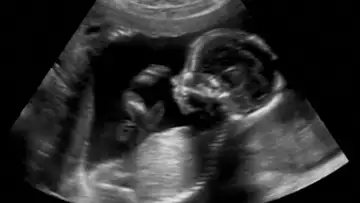

Fetal Surgery

Fetal SurgeryMay 11, 202114mAdvances in medical procedures allow surgeons to operate on infants while they are in the womb to help prevent or treat birth defects.

Advances in medical procedures allow surgeons to operate on infants while they are in the womb to help prevent or treat birth defects.